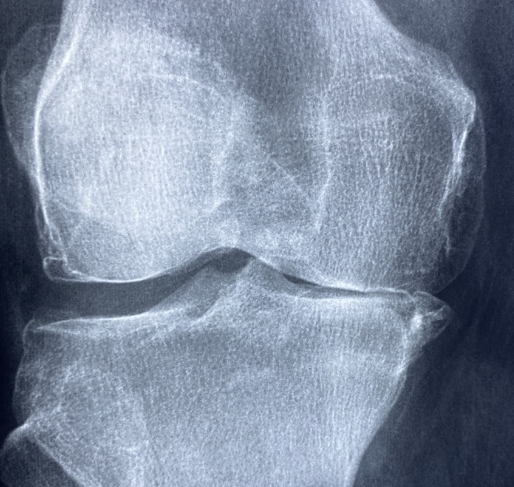

1. 퇴행성 관절염

원인: 관절 연골의 손상으로 인해 발생하며, 주로 노화와 관련이 있습니다.

증상: 오래 걷거나 서 있을 때, 계단을 오르내릴 때, 쪼그려 앉을 때 통증이 심해집니다. 밤에 통증으로 잠을 자기 어려울 수 있습니다.

퇴행성 관절염은 관절 연골의 점진적인 소실로 인해 발생하는 가장 흔한 관절 질환입니다.

주로 50세 이후에 발병하며, 여성에게 조금 더 높은 확률로 나타납니다.

▶ 노화, 비만, 과도한 관절 사용, 반복적인 외상 등이 원인이 될 수 있습니다.

▶ 아침 증상은 거의 없거나 15분 이내로 지속됩니다.

▶ 움직일수록 통증이 심해지며, 오전보다 오후에 더 심한 경향이 있습니다.

▶ 주로 무릎, 골반, 척추 등 체중을 지탱하는 관절에 영향을 미칩니다.